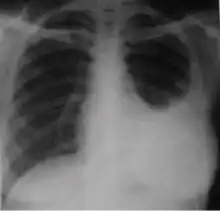

Chest x-ray of pleural thickening post-primary tuberculosis

1. Pleural thickening - Irregularity or abnormal prominence of the pleural margin, including apical capping (thickening of the pleura in the apical region). Pleural thickening can be calcified.